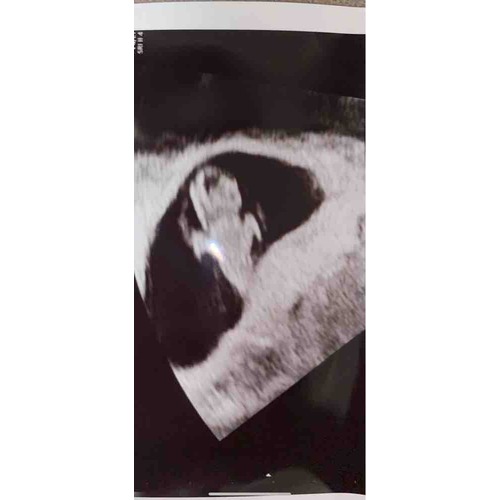

7+4🥰

Ze hebben het hartje niet laten horen omdat het blijkbaar slecht was, maar we zagen het hartje wel kloppen🥰